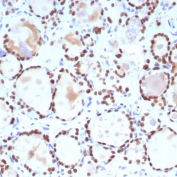

IHC staining of FFPE human thyroid tissue with TTF-1 antibody (clone NX2.1/9035). Inset: PBS used in place of primary Ab (secondary Ab negative control). HIER: boil tissue sections in pH 9 10mM Tris with 1mM EDTA for 20 min and allow to cool before testing.

IHC staining of FFPE human thyroid tissue with TTF-1 antibody (clone NX2.1/9035). HIER: boil tissue sections in pH 9 10mM Tris with 1mM EDTA for 20 min and allow to cool before testing.